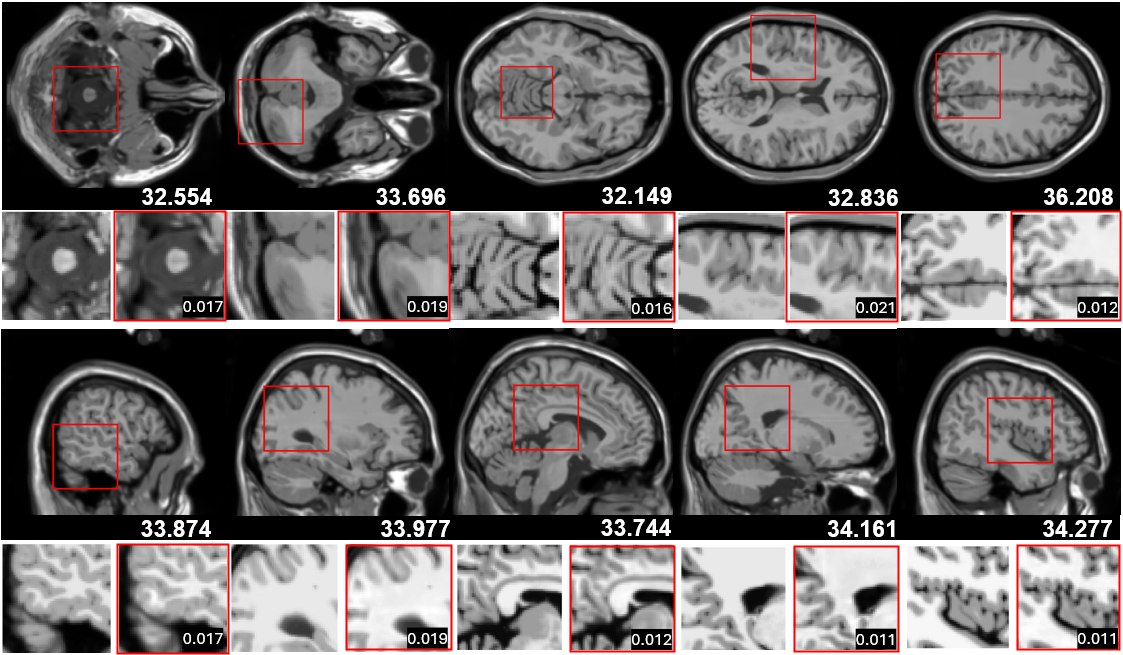

With the experimental setup described above, the reconstruction results are summarized in Table 2, and qualitative reconstruction results of axial and sagittal views are shown in Figure 2. A detailed comparison between the rendered outputs and ground truth is provided in Appendix 6. Our method successfully reconstructs fine anatomical structures, such as cortical folds and deep brain boundaries, while preserving smooth transitions in homogeneous areas like white matter or cerebrospinal fluid.

Refer to caption

Figure 2: Brain MR reconstructions in axial (top) and sagittal (bottom) views. The top row shows test set renderings with PSNR values overlaid. Red boxes highlight regions for detailed reconstruction. In each zoom-in region, the left patch is the ground truth, and the right is the prediction, with L1 errors indicating absolute differences within the region.

Figure 6 presents the reconstruction results of brain MRI images in three anatomical planes. From top to bottom, the figure shows the sagittal, axial, and coronal planes, respectively. In each set of images, the top row displays the model’s predicted images (pred), while the bottom row shows the corresponding ground truth images (gt). The predicted images are annotated with their PSNR values to quantify reconstruction quality. It can be observed that the model successfully reconstructs the brain anatomy across all planes, with clear details of gyri and sulci, and demonstrates high consistency with the ground truth in terms of contrast and structural details, indicating strong reconstruction capability.

Figure 6: Brain MR reconstructions in different anatomical planes. From top to bottom are the axial, sagittal, and coronal views, respectively.